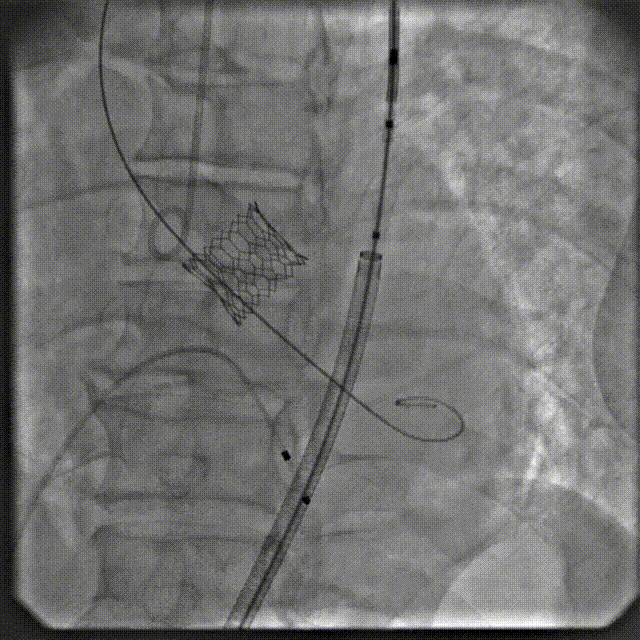

手术过程

根部造影

跨瓣

瓣膜系统过弓

定位造影

瓣膜确认位置后释放

回收极限处造影

最终造影

术后复查造影示瓣膜位置满意,形态良好,冠脉显影良好;TTE示轻微瓣周漏;排除入路血管问题,手术圆满成功。